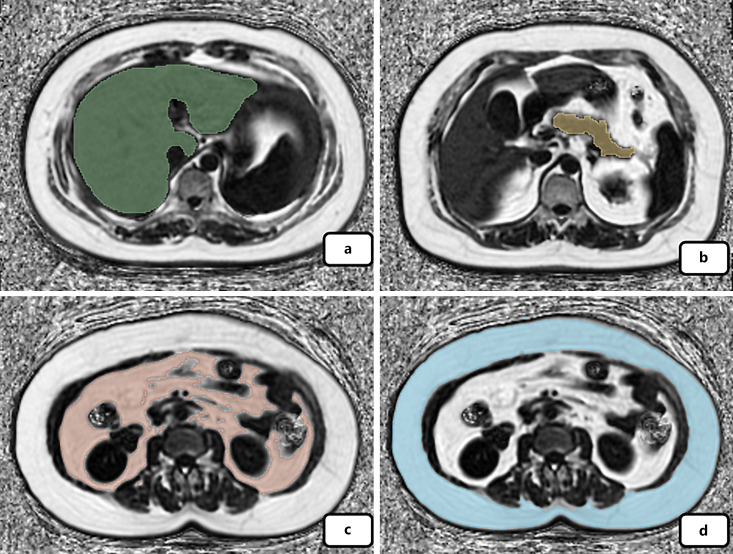

Methods: A total of 98 subjects were enrolled; there were 53 cases in the normal glucose metabolism group and 45 cases in the abnormal glucose metabolism group. Chemical shift-encoded magnetic resonance imaging was applied for quantification of pancreatic fat fraction (PFF) and hepatic fat fraction (HFF), subcutaneous adipose tissue (SAT), and visceral adipose tissue (VAT). The correlation and the difference of fat distribution between different metabolism groups were analyzed. The receiver operating characteristic (ROC) curve was used to analyze the suggestive effect of different body fat fraction.

Results: Correlation analysis showed that body mass index (BMI) had the strongest correlation with fasting insulin (r = 0.473, p < 0.001), HOMA-IR (r = 0.363, p < 0.001), and C-reactive protein (r = 0.245, p < 0.05). Pancreatic fat has a good correlation with fasting blood glucose (r = 0.247, p < 0.05) and HbA1c (r = 0.363, p < 0.001). With the increase of BMI, PFF, VAT, and SAT showed a clear upward trend, but liver fat was distributed relatively more randomly. The pancreatic fat content in the abnormal glucose metabolism group is significantly higher than that in the normal group, and pancreatic fat is also a reliable indicator of abnormal glucose metabolism, especially in the normal and overweight groups (the area under the curve was 0.859 and 0.864, respectively).